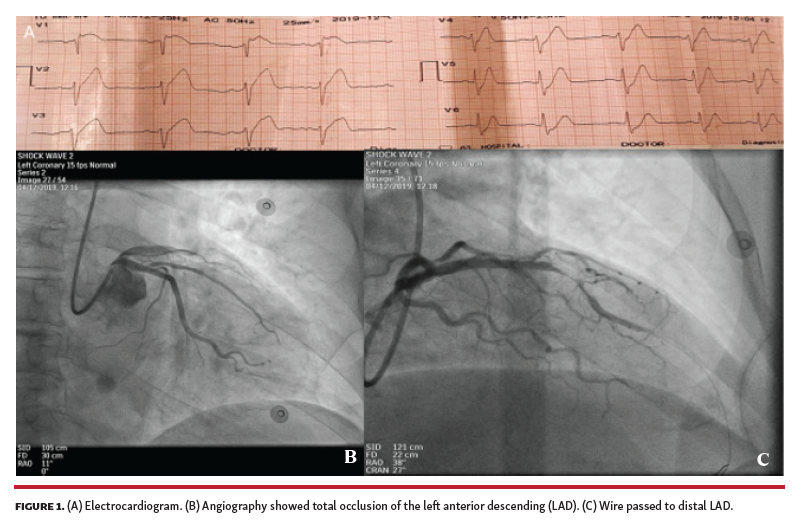

After several attempts with 2.0 x 15 mm and 2.5 x 15 mm compliant and non-compliant balloons used for predilation, a significant residual stenosis remained (Figure 2). At that time, we decided to use Shockwave intravascular lithotripsy (IVL; Shockwave Medical). A 3.00 x 12 mm lithotripsy balloon was chosen, but proved too bulky to advance and deliver. Guide-extension catheter improved support, and 4 cycles of lithotripsy were delivered, achieving full expansion (Figure 3). Subsequently, a 3.0 x 24 mm drug-eluting stent was delivered and deployed, with an optimal result (Figure 4).